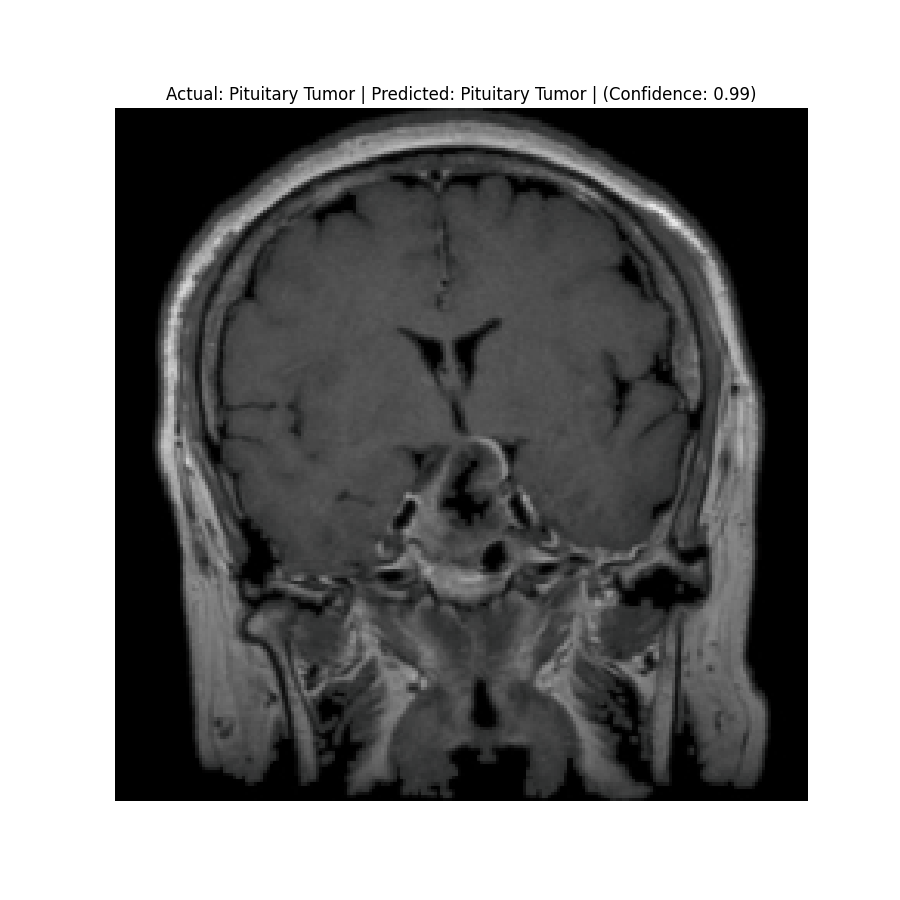

The dataset used in this project is the Brain Tumor Classification (MRI). It consists of MRI scans categorized into four classes: 👇

Glioma Tumor | Meningioma Tumor |

Normal | Pituitary Tumor |

Results

Check the predictions in the predictions folder. Below are some sample results:

![]() Actual: Normal Predicted: Normal (Confidence: 0.98) | ![]() Actual: Pituitary Tumor Predicted: Pituitary Tumor (Confidence: 0.99) |